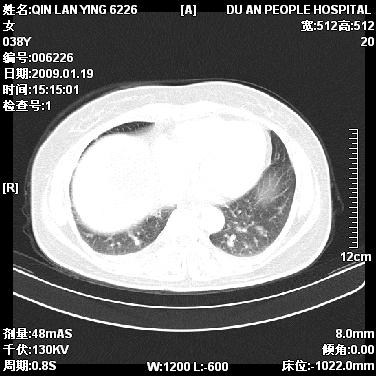

女,38岁,胸疼1个月。wbc:1万4

1)右肺中央型肺癌并右肺上叶阻塞性肺炎、节段性肺不张,纵隔淋巴结转移、右侧胸膜转移、肝脏转移。2)右侧胸腔少量积液。

1、右侧中央型肺癌并阻塞性肺不张,纵隔内、主动脉弓旁、右肺门淋巴结及肝脏转移可能性大,建议纤支镜进一步检查。

2、右侧胸腔积液。

本病例有几个容易诊断的地方:1、右肺上叶前段支气管闭塞,肺不张。2、淋巴结明显肿大。3、肝脏多个类圆形低密度影呈“牛眼征”改变,高度提示转移。

从影像学角度分析      右肺上叶中央型肺癌,并阻塞性不张、肺炎,纵隔淋巴结、膈顶淋巴结转移。

肝内两个大小不等低密度结节,内可见更低密度影,首先考虑肝内转移瘤,但联想到患者wbc1万4,建议楼主还是做个增强比较明确,除外肝脓肿的可能。